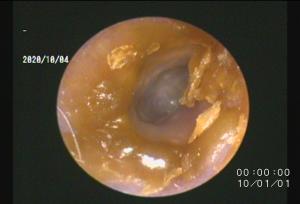

正常な耳内はこのように綺麗です

上記の写真は正常な耳道の写真です↑